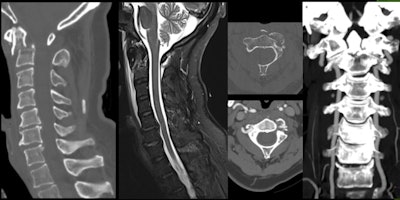

A 28-year-old woman suffered trauma during sledging. Acute fracture of L1 vertebral body with height loss and small backward retreat of posterior wall, as well as multifragmentary sacral fracture, prevertebral, and presacral hematomas. Residual right L5 radiculopathy after surgical fixation."Spinal injuries are a major cause of permanent disability and appear to be increasing among skiers and snowboarders," the researchers said. "Spinal injuries in skiers have been traditionally much less common than in snowboarders, but this disparity is likely to diminish with the recent trend of incorporating snowboarding moves into skiing."

Cervical pain in 57-year-old man after ski fall. Fracture of base of C2 odontoid process with lesion of anterior longitudinal ligament, prevertebral hematoma, and narrowing of left vertebral foramen, without arterial dissection.Even in the absence of skull or cervical fractures, patients may present with vascular injuries, so a high degree of suspicion is required from the examiner. Mechanisms of hyperflexion, hyperextension, acceleration, or deceleration should raise a red flag and elicit a more comprehensive investigation. In the acute setting, CT angiography is preferred over MR angiography if the patient presents with one of these mechanisms and/or skull base fractures and/or cervical fractures involving the vertebral foramina.